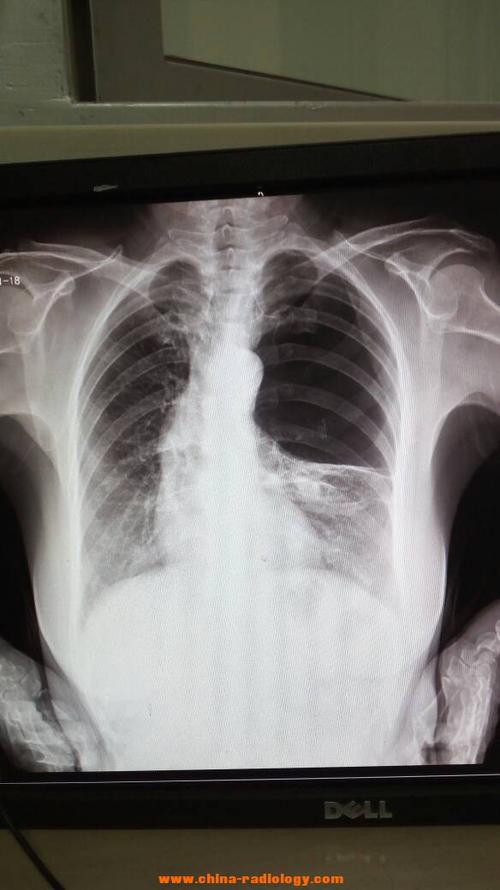

肺大泡胸片

肺大泡x线图片

肺大泡x线表现图片